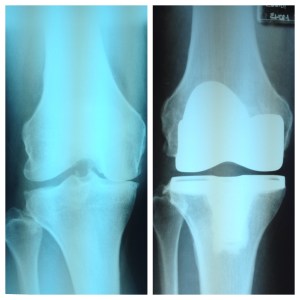

We spent the winter in San Tan Valley, Arizona, which is between Phoenix and Tucson. On January 13, I had a total knee replacement. I’m not going to lie; that wasn’t a lot of fun. Recuperating in an RV can be challenging, but I was able to spend the first week after surgery at our Aunt Dawn’s house. It was perfect; we had our own room, there were no stairs and she spoiled me rotten with chicken soup, chocolate pudding and fresh grapefruit—right off the tree and into my breakfast. I’m a big fan of fresh grapefruit!

Knee replacements have come a long way, baby. Mine was an outpatient procedure. We arrived at the surgi-center at 6 a.m. By 11, I was wobbling around with a walker and at 1 p.m. we were settling in at Aunt Dawn’s place. An I.V. nurse, a home health nurse and a physical therapist came by frequently to take care of me. The outpatient option is fairly new; I was my surgeon’s 24th patient to try it. There were also no stitches or staples in my incision; it was glued together and covered with a single piece of gauze. You know it’s uncommon when the nurses are surprised.